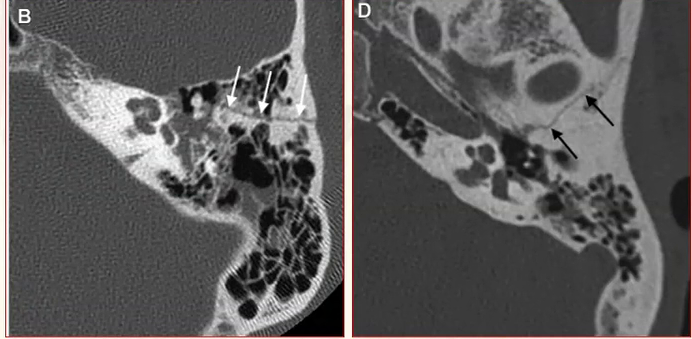

Cite o checklist de estruturas que devem ser avaliadas em uma tomografia de um trauma de osso temporal, como as abaixo.

A

• Localização e linha de fratura do osso temporal

• Capsula óptica e vestibulo

• Cadeia ossicular

• Canal e trajeto do facial

• Tégmen Timpânico

• Estruturas vasculares (carótida, seio sigmoide, transverso, bulbo da jugular).

Quais sinais INDIRETOS de trauma temporal são observados nas imagens abaixo, além da linha de fratura em si?

• Ar na região intracraniana, adjacente ao osso temporal

• Ar na articulação temporomandibular

• Pneumolabirinto

• Opacificação de células da mastóide

• Opacificação do CAE